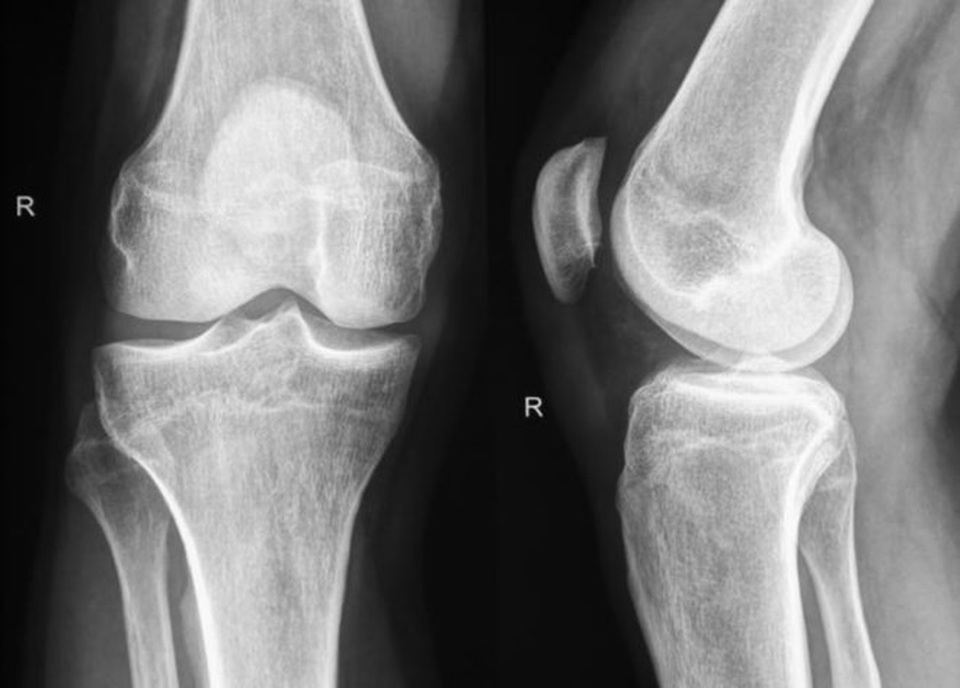

Tái tạo xương và sụn nhờ nano-biomaterials

Xương và sụn là những mô có khả năng phục hồi hạn chế, đặc biệt ở người lớn tuổi. Công nghệ nano đã mang đến hy vọng mới.

Vật liệu composite chứa hạt nano hydroxyapatite mô phỏng cấu trúc xương tự nhiên, giúp tăng độ bền và khả năng tái tạo.

Theo thống kê từ Journal of Orthopaedic Research, các ca cấy ghép sử dụng khung nano cho thấy tỷ lệ phục hồi

thành công cao hơn 30% so với phương pháp cấy ghép truyền thống. Điều này đặc biệt hữu ích trong điều trị gãy xương phức tạp,

bệnh loãng xương hoặc thoái hóa khớp.